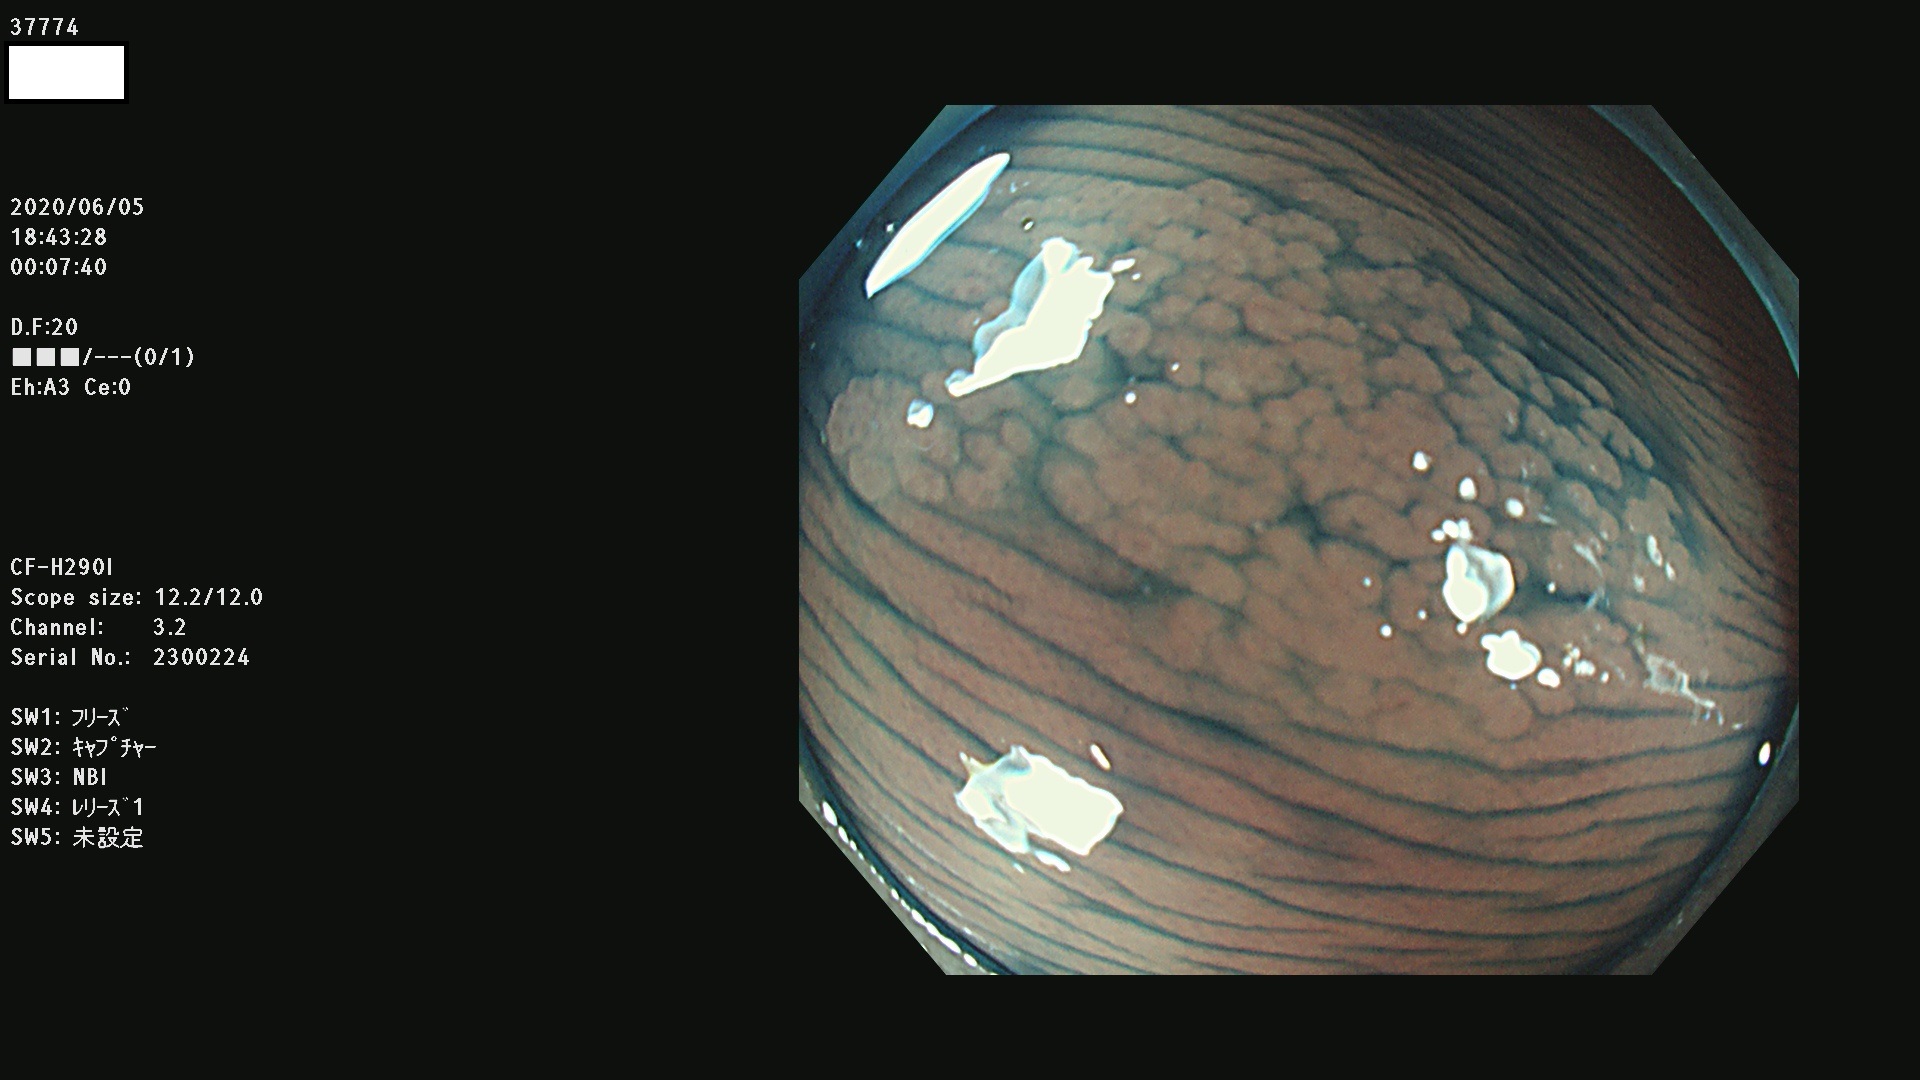

37700 37701 37702 37703 37704 37705 37706 37707(SSAPのみ) 37709 37711 37712 37715 37716 37717 37720 37722(SSAPのみ) 37724 37725 37726 37727 37728 37729 37731 37732 37733 37736(SSAPのみ) 37737 37739 37740 37741 37742 37744 37745 37748 37749 37750 37751 37752(SSAPのみ) 37753 37754 37755 37757 37758 37760 37761 37762(SSAPのみ) 37763 37764 37765 37766 37767 37768 37769 37771 37772 37774 37775 37776 37777 37780 37781 37782 37783 37784 37785 37787(SSAPのみ) 37788 37791 37792 37793 37794 37795 37799

発見困難で危険性の高い平坦型病変(上記100名より抽出)